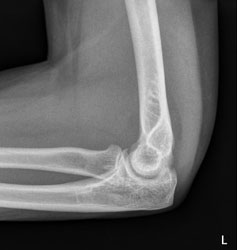

Eine 37 Jahre alte Frau stürzt auf dem Eis zu Boden und stützt sich mit dem linken Arm noch ab. Wegen Schmerzen im linken Ellbogen geht sie zum Arzt, welcher das folgende Röntgenbild macht.

Der erstbehandelnde Arzt sieht auf dem Röntgenbild keine Fraktur und verordnet der Patientin Schmerzmittel. Weil die Schmerzen aber nicht bessern, meldet sich die Patientin wieder und das Röntgenbild wird noch einmal beurteilt:

Ellbogen seitlich

Wie beurteilen Sie das Röntgenbild?